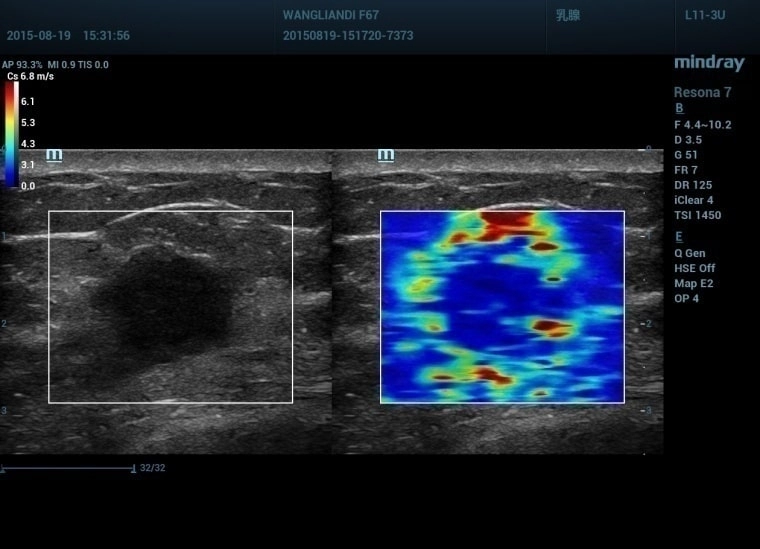

Эластография

Эластография – относительно новый метод ультразвуковой диагностики.

С его помощью врачи могут оценить плотность мягких тканей или отдельных органов.

Процедура относится к высокоточным диагностическим манипуляциям – диагноз оказывается верным в 95% клинически фиксируемых случаев.

Общие сведения о сдвиговой эластографии

Эластографию следует считать одним из видов ультразвуковых исследований. Программное обеспечение диагностического компьютера оценивает упругость тканей человеческого организма на основании данных, получаемых от УЗ-сканера. Принцип работы системы основан на уровне эластичности, который характерен для всех внутренних органов детей и взрослых. Патологические изменения в тканях приводят к нарушению их строения и утрате прежних характеристик упругости.

Основным способом определения эластичности тканей на протяжении длительного времени оставалась пальпация. Но ее диагностические возможности ограничены. Эластография становится визуальным воплощением пальпаторных методов. При этом ультразвук обладает существенно большей глубиной проникновения – врачи могут определить состояние внутренних органов человека.

Достоинство УЗИ с эластографией заключается в возможности оценить злокачественность новообразований без забора биоптата. При подтверждении локации очага рака врачам предстоит выполнение биопсии для проведения гистологического исследования. Отсутствие признаков малигнизации опухоли позволяет избавить пациента от инвазивной диагностической процедуры.

Расшифровка показателей

Здоровые органы относительно легко деформируются из-за воздействия ультразвука и возвращаются в исходное положение. Раковые опухоли не обладают такими свойствами – их отличает большая плотность и отсутствие реакции на звуковые колебания. Эта особенность злокачественных образований становится основой для интерпретации результатов эластографии.

Расчет параметров упругости исследуемой области осуществляется компьютером. Специалист по ультразвуковой диагностике изучает полученные данные и формирует заключение, описывает состояние всех тканей, подвергшихся изучению. При выявлении очагов рака онкологи назначают пациенту дополнительные анализы: проводится биопсия, компьютерная и магнитно-резонансная томографии, пункции и т.д.